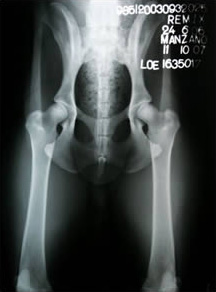

Caderas: Libre

Ch. Remix de Pomerland - Caderas